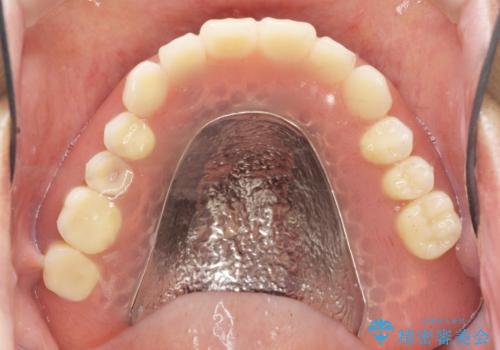

保存可能な2本の歯を用いて、マグネットデンチャー(磁性アタッチメントを用いた入れ歯)による治療を行いました。

予算を抑えて審美的に咬合を回復することができ、ご満足頂けました。

マグネット(磁石)により入れ歯がはずれにくく動揺しにくいため、入れ歯安定剤などを使うことなく食事やお話も問題なくできると喜んで下さいました。

入れ歯の種類:金属床義歯 マグネットデンチャー